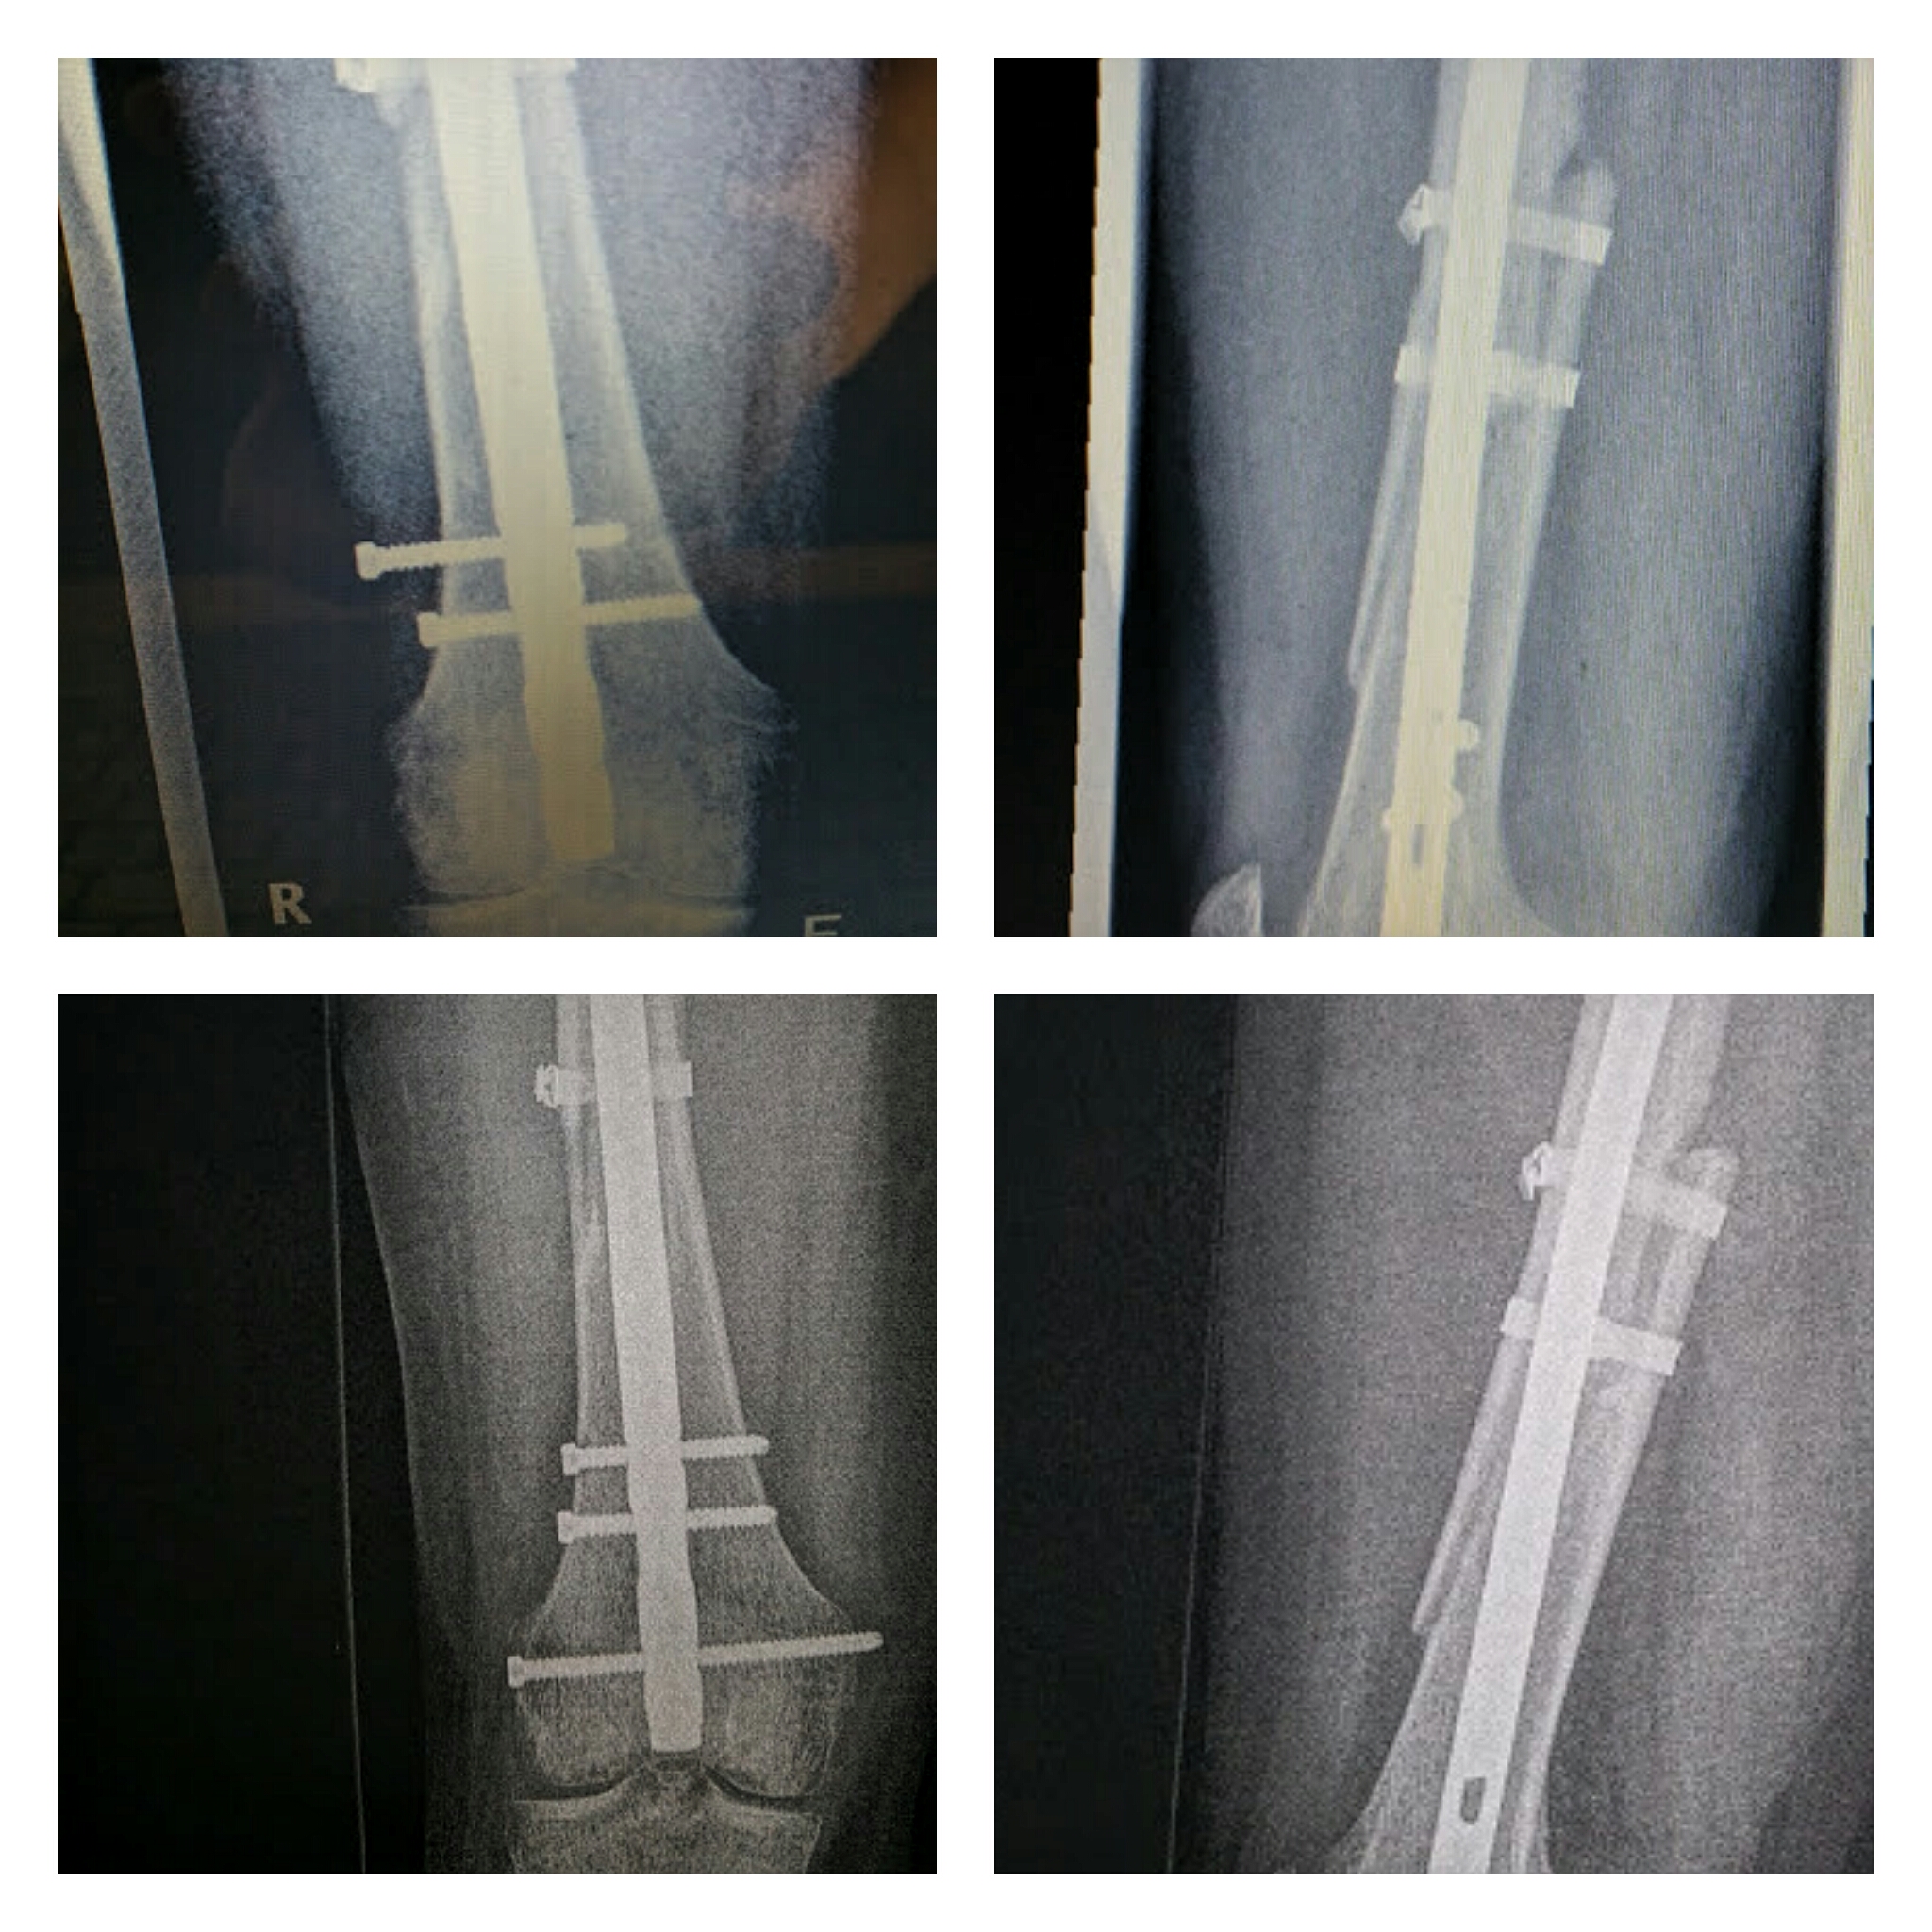

Wie Lange Dauert Die Heilung Nach Einem Schienbeinbruch